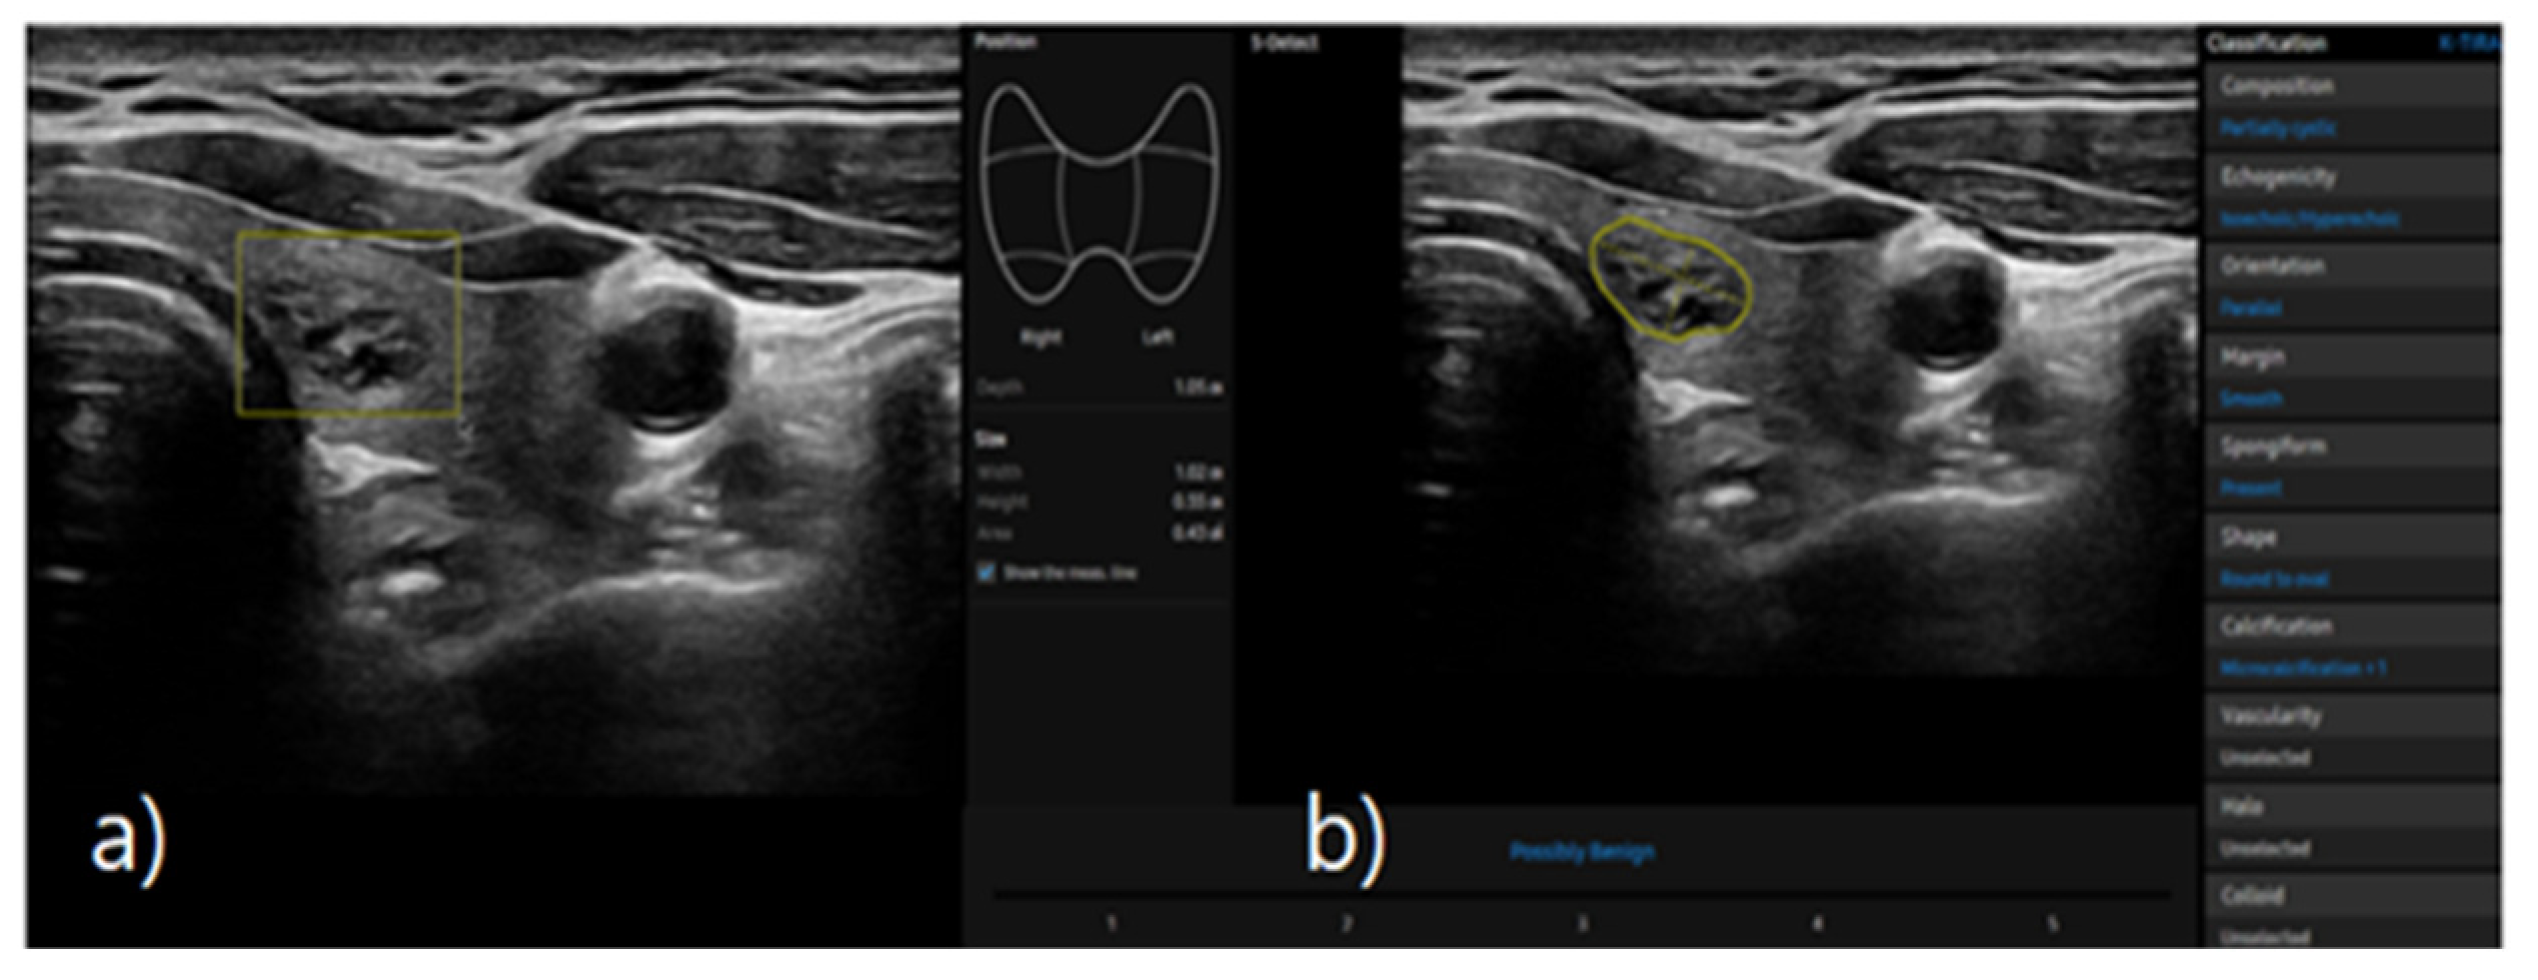

S-detect is an AI-based CAD software for analyzing ultrasound images. When the region of interest for the targeted nodule is established, the software automatically identifies the boundaries and begins the analysis [16,19]. The nodules were classified as possibly benign or possibly malignant based on characteristics such as internal composition, echogenicity, orientation, margin, and shape. This case is depicted in Figure 2.

Figure 2. a) Ultrasound grayscale transverse image of the left thyroid lobe in a 57-year-old woman. b) Thyroid nodules automatically classified as benign and malignant using S-detect according to characteristics such as internal composition, echogenicity, orientation, margin, and shape.